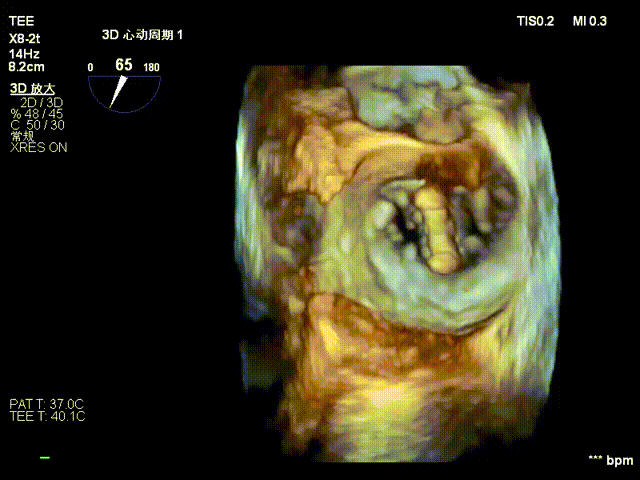

术前心超提示:

退行性二尖瓣反流(DMR),A2-A3脱垂伴连枷样运动(脱垂范围:17mm,连枷间距:7mm),P3脱垂,反流主要位于2-3区,MR重度4+(VC:6*17 mm),A3:18mm,P3:9mm,A2:24mm,P2:14mm,AP:32mm,二尖瓣口面积MVA约 5.6cm²,左房、左室明显扩大。

术中操作(关键步骤超声)

在全麻下,于心尖入路完成ValveClamp®装置植入。术中多学科团队密切配合,超声全程实时指导操作。最终,于2偏3区成功植入一枚Ⅲf夹子,一次夹合完成。前叶夹合量12mm,后叶夹合量10mm,反流降至1+,导管操作时间30分钟。术后平均跨瓣压差3mmHg。